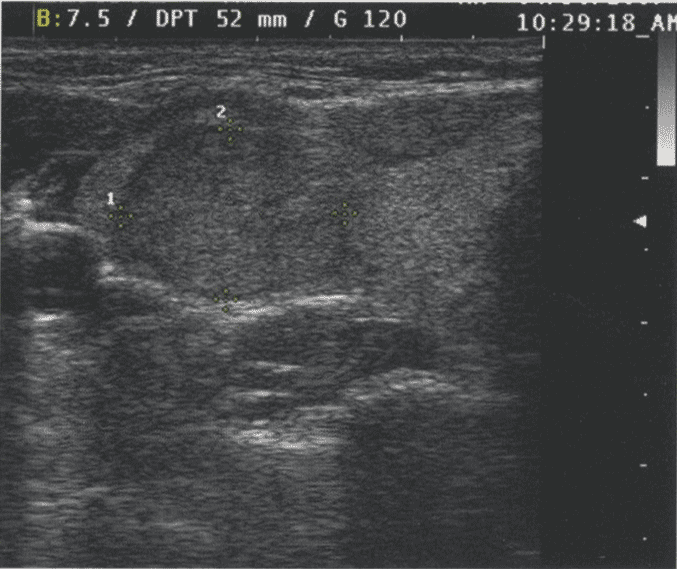

И хотя более высокие частоты дают лучшее разрешение, глубина визуализации с увеличением частоты снижается. В современных УЗ-аппаратах для исследования ЩЖ используется достаточно высокая частота — 16 МГц. Однако при этой частоте исследование можно провести лишь на глубину до 5 см. Визуализация более глубоких структур, как и при УЗИ органов брюшной полости или малого таза, требует более низкой частоты. У тучных пациентов или при исследовании очень глубоких структур для адекватного проникновения луча и визуализации глубоких структур шеи может потребоваться частота 5-7,5 МГц. На рис. 2.22 и рис. 2.23 сравниваются изображения при частоте 7,5 и 13 МГц. Видно, что детализация проксимальных структур при более низкой частоте снижается.

Рис. 2.22. Сравнение изображений, сделанных при частоте в 7,5 и 13 МГц. При использовании датчика с частотой 7,5 МГц узел определяется менее четко, но структуры кзади от него визуализируются лучше. Сравните с рисунком 2.23